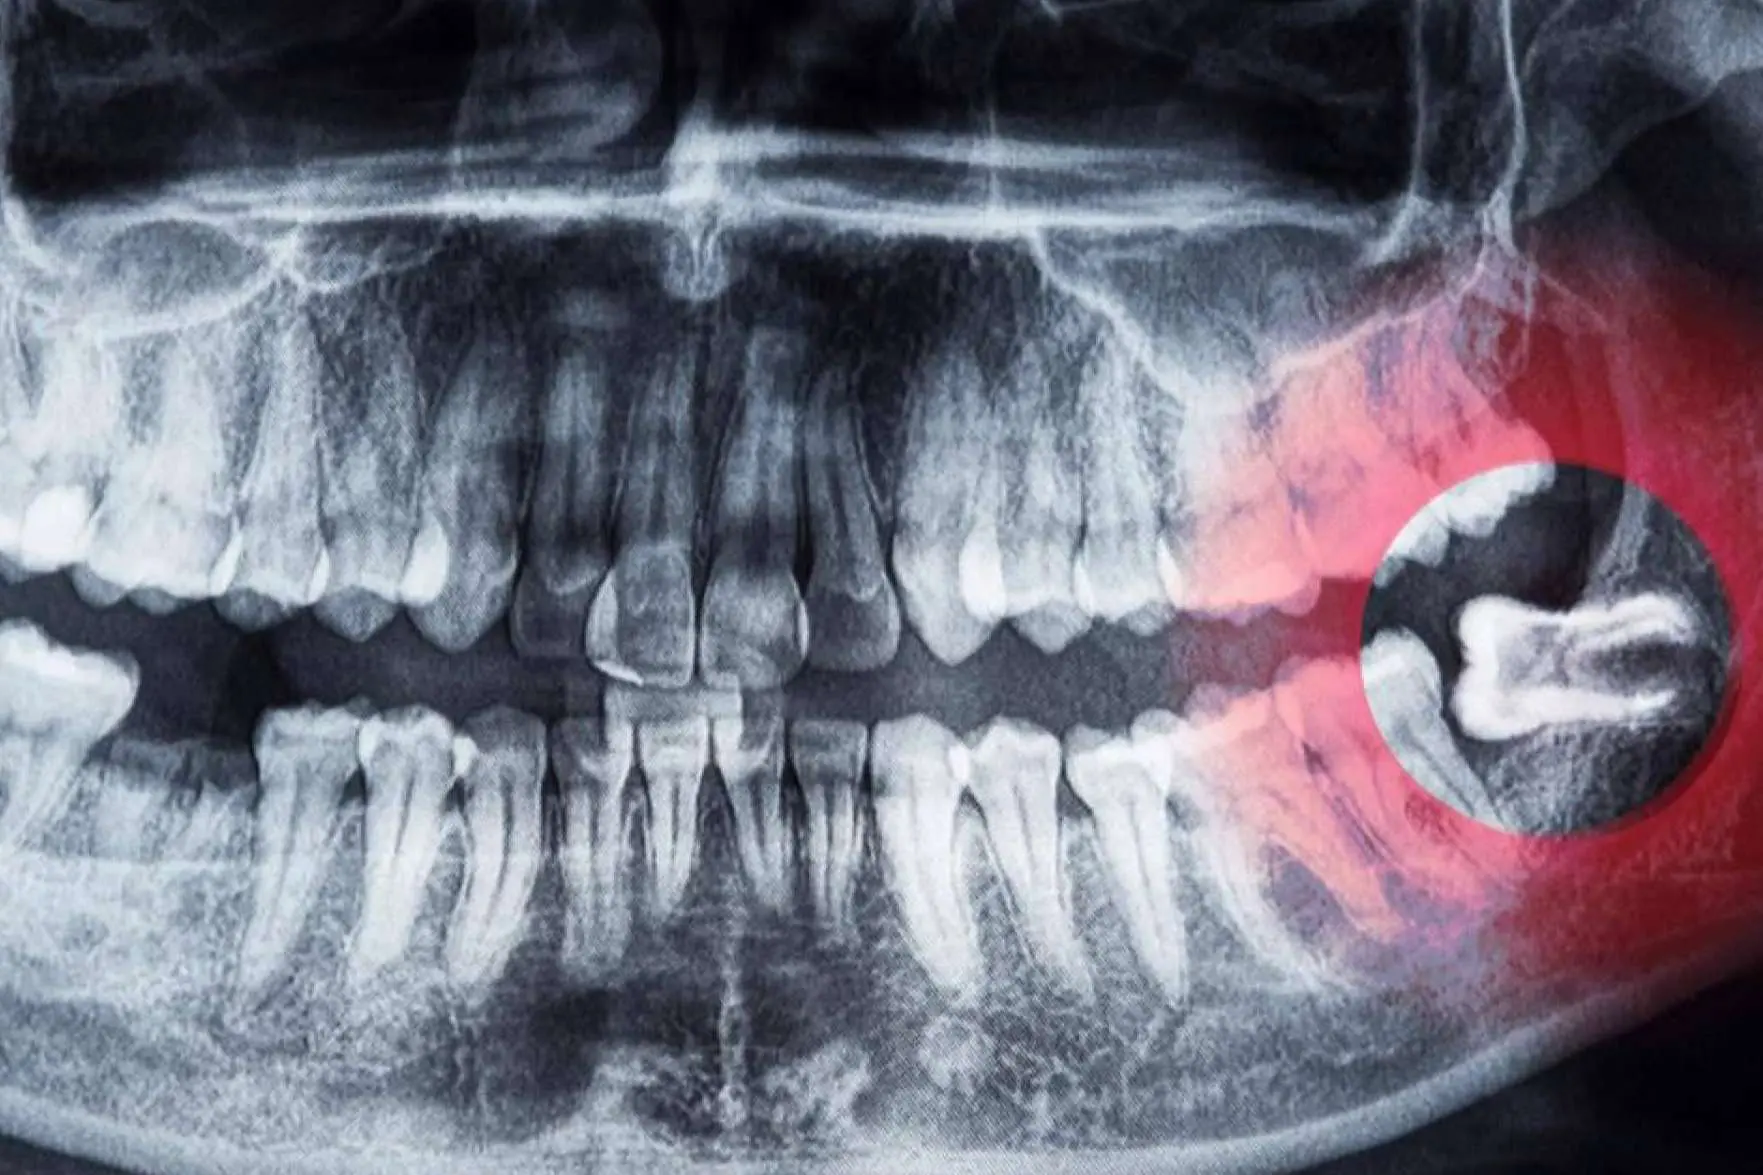

Las cordales o terceros molares son las últimas muelas que suelen aparecer en la boca a una edad comprendida entre los 17 y los 25 años.

En algunas personas, las cordales nunca llegan a brotar y, en otras, pueden causar problemas debido a su posición. En los casos de mayor gravedad, los especialistas recomiendan la extracción de los molares si existe algún cambio en la zona donde están esas muelas, por ejemplo: dolor, infección o quistes. Dicho procedimiento siempre debe ser realizado por un especialista en cirugía bucal y maxilofacial, ya que pueden presentarse complicaciones si el procedimiento no es correctamente realizado. Actualmente, existen clínicas de salud dental dedicadas a la extracción de cordales, como es el caso de Cibumaxi.

En este sentido, una de las causas más comunes para extraer las cordales son las infecciones como la pericoronitis o las caries. Asimismo, se recomienda en pacientes que presenten quistes, ulceraciones o traumatismos en las encías. La exodoncia también es habitual durante tratamientos de ortodoncia para la alineación de los dientes.

Los odontólogos también advierten que los terceros molares retenidos pueden causar graves problemas en la salud dental. Los dolores agudos, lesiones dentales y encías hinchadas son las consecuencias más frecuentes. Además, algunas personas pueden experimentar inflamación en la mandíbula, formación de quistes, tumoraciones, neuralgias y dificultad para abrir la boca.